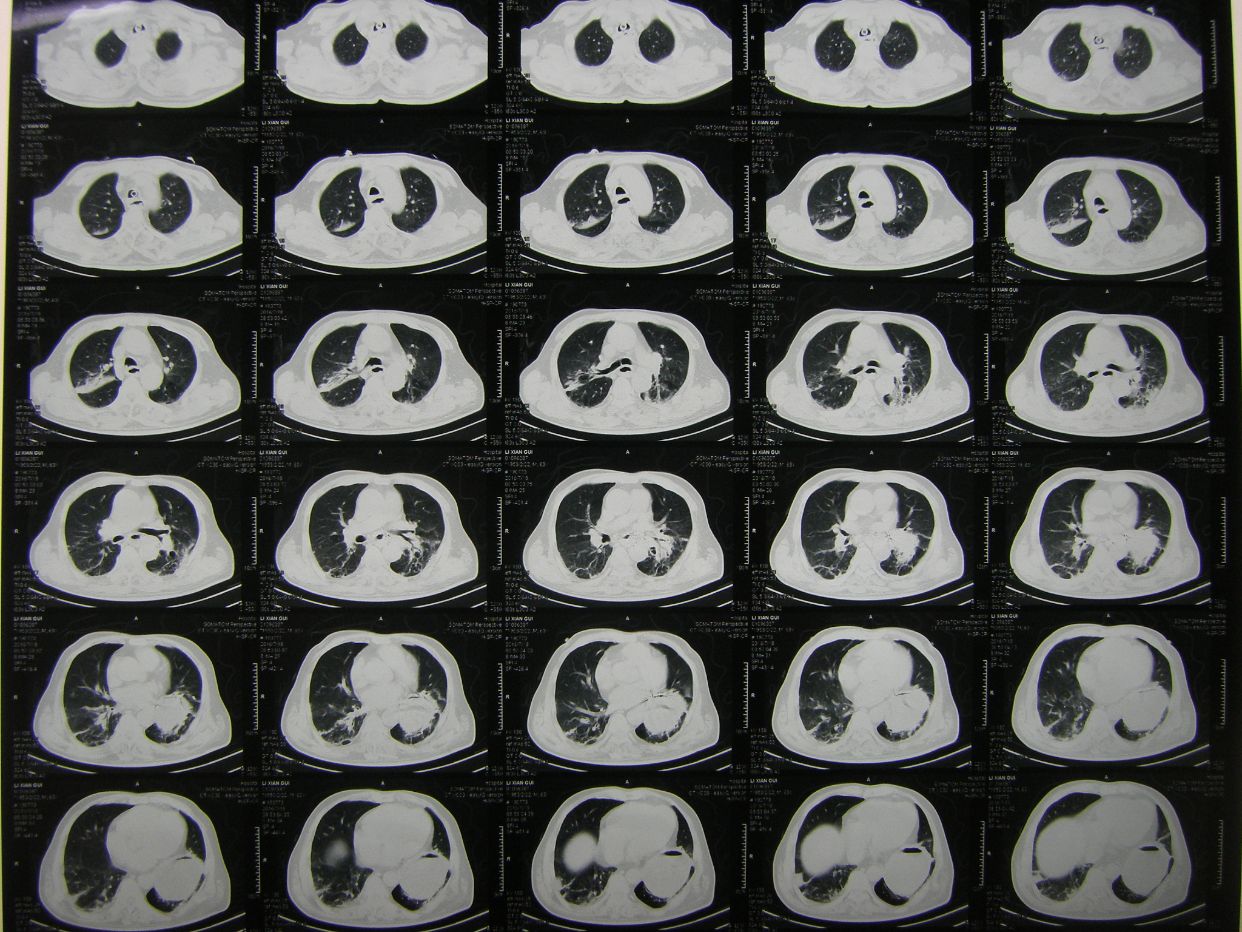

因呼吸急促,氧饱和度低,行胸部CT检查示,双肺野弥漫性斑片状阴影,保留气管插管,拍背吸痰,加强供氧,应用抗炎平喘化痰等药物治疗。

查血气分析示,丨型呼吸衰竭并呼碱,给予呼吸机辅助呼吸。

术后半月胸部CT复查示,肺部阴影消退。患者体温血象正常,神志清,遵嘱动作,右侧肢体肌力3级,出院康复。

术后8天,患者出现呼吸困难,氧饱和度下降,胸部CT示左侧肺野消失,考虑胃膈疝并肺不张肺感染。调整体位,拍背吸痰,应用呼吸机辅助呼吸等治疗。

胸部CT复查,肺不张恢复,肺部阴影消退。患者恢复意识,遵嘱动作,呼吸良好,体温血象正常,出院康复。